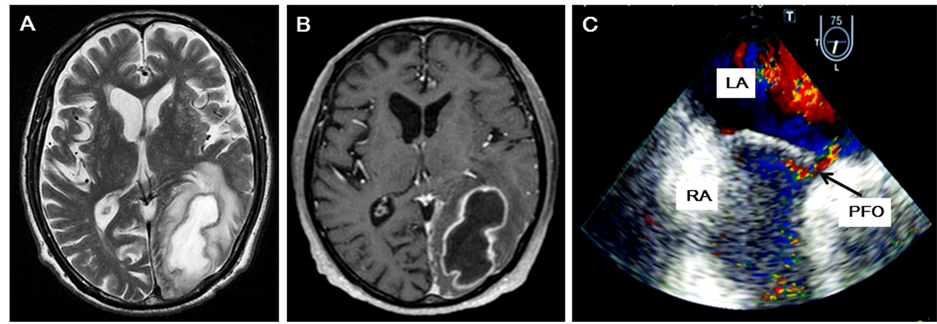

Figure 1. (A)-(C) Brain magnetic resonance image (MRI) with Geranium enhancement (A) and (B) and transesophagial echocardiogram (TEE) findings (C). (A) T2-weighted axial MR image showing a heterogeneous mass in the left occipital lobe, compressing the left lateral ventricle; (B) T1-weighted axial MR image with gadolinium enhancement, showing a left occipital hypointense mass lesion with ring enhancement; (C) TEE demonstrating PFO. A large right-to-left shunt identified by color Doppler analysis without Valsalva maneuver. RA: right atrium, LA: left atrium.

arteriovenous fistulas. Echocardiography revealed no potential risk factors, such as endocarditis, vegetation, or pulmonary hypertension. We diagnosed the case as having a cryptogenic brain abscess, and performed further examination to investigate the cause of the abscess. Transesophageal echocardiography detected a PFO, permitting a right-to-left shunt without Valsalva maneuver (Figure 1(C)). The patient’s oral hygiene was maintained. Antibiotic therapy continued for 6 weeks after drainage, and the brain abscess almost disappeared. He was discharged from the hospital 2 months after admission, with right homonymous hemianopsia as the persisting neurological sequela.